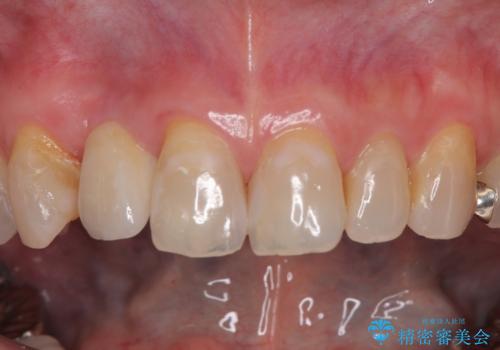

新幹線や飛行機を利用しても来院であり、極力来院回数を減らしたり、東京に用事があるタイミングに合わせてアポイントを調整したりと、負担が少なくなるようにして治療を進めて行きました。

来院間隔があいたため、予定よりも長くなりましたが、大きなトラブルもなく、外科処置は1回のみ、最小の来院数で無事に治療を終えることができました。